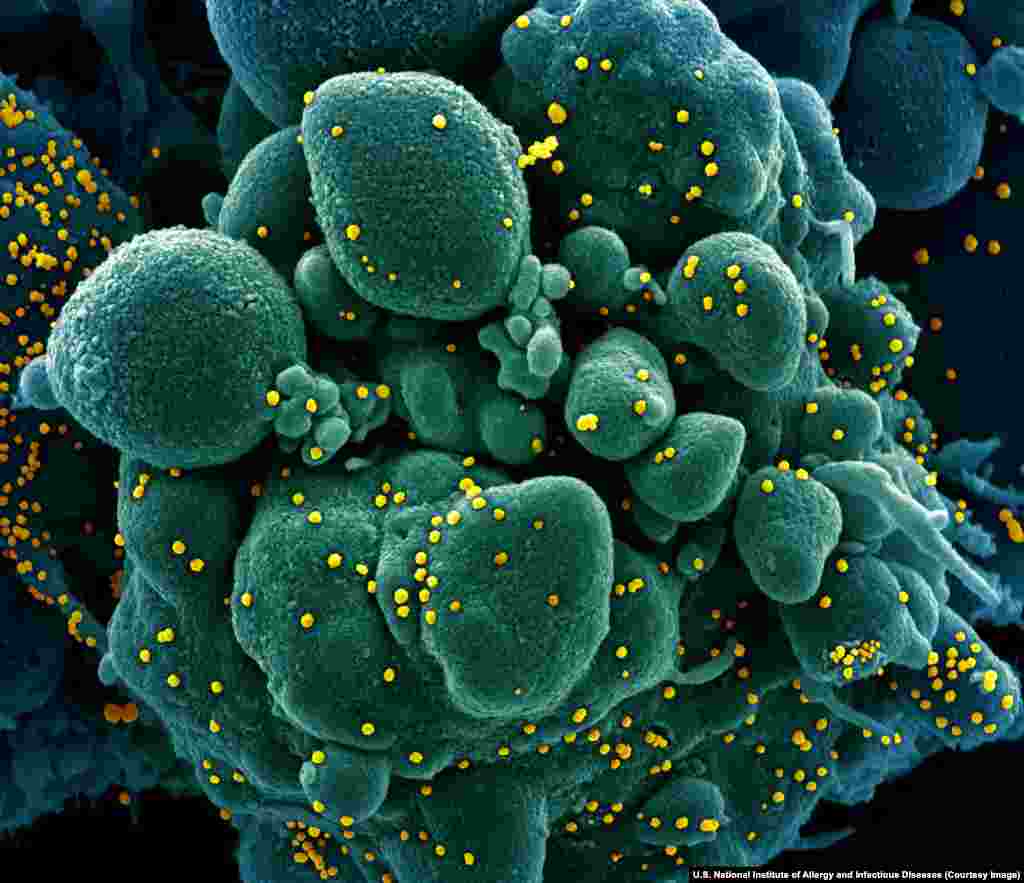

3

Koronavirusi i ri duke përfshirë sipërfaqen e një qelize njerëzore. Koronaviruset janë familje e patogjeneve vrasëse sikurse SARS dhe MERS, por edhe një varg llojesh tjera virusesh kryesisht të padëmshme.